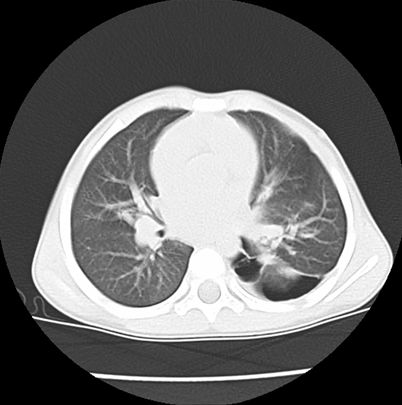

We asked for a Chest CT scan